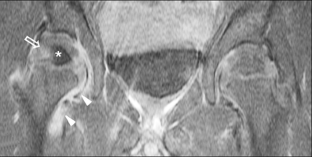

Fig. 3